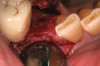

Figure 12  A patient who had tooth No. 2 extracted using Piezosurgery, periotomes, thin-bladed elevators, and small-beaked forceps, enabling preservation of all bony peaks.

Figure 12

Figure 13  After debridement of the socket, a mixture of pure-phase β-TCP and heme from the surgical site was covered with a dense polytetrafluoroethylene (PTFE) barrier.

Figure 13

Figure 14  At the time of the 6-month reentry, the site appeared healed. Full ridge height preservation and graft resorption with bony replacement were confirmed radiographically.

Figure 14

In previous papers on dental extraction therapy with or without immediate socket implants, site collapse in a buccolingual dimension was ≥ 50% for a 6-month period. Studies have demonstrated preservation of alveolar dimensions after extraction socket grafting.24-26 These studies showed no treatment of the socket resulted in a collapse of the alveolus by 29% and grafting the socket at the time of extraction resulted in bone loss of only 13%.24 The average loss of alveolar width in the grafted sites in this study was 12%. Numerous papers state that one of the reasons to place an immediate socket implant is to preserve the alveolar ridge width. That statement is not borne out consistently in the conclusions of the authors. One recent paper, in which reentry was performed at the time of dental implant uncovering, offers an alternative conclusion. In that paper, implants were placed after extraction of single-rooted teeth. After averaging the ridge width changes, it was noted that there was a 35.2% loss of bone volume in the buccolingual dimension.25 Similar evidence of socket collapse after placement of immediate socket dental implants questions the use of this technique to preserve alveolar bone volume.26 The results of this current study clearly demonstrate a significantly better maintenance of alveolar ridge dimension than the placement of an immediate socket dental implant with no grafting (Figure 12 through Figure 14).